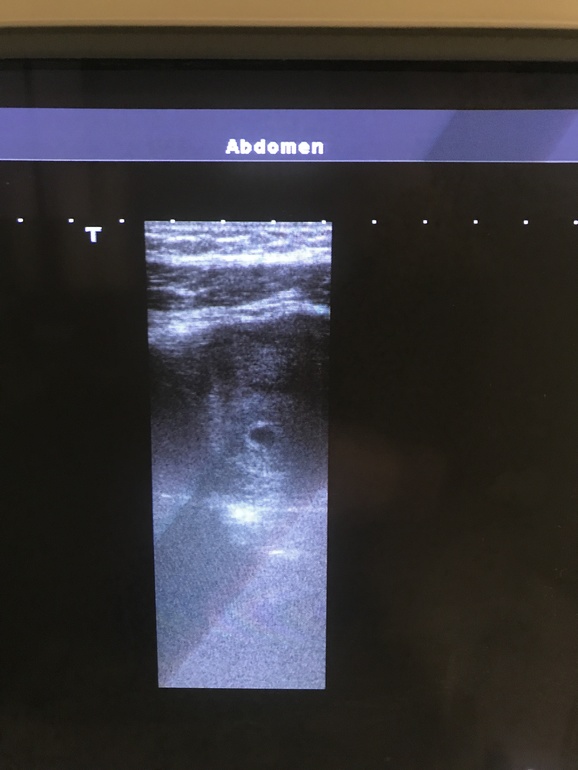

У нас получилось! Я беременна!Как же я мечтала написать такой пост именно в этом сообществе❤️ По узи нам 4-5 неделек, сегодня было второе узи, так как на первом сказали, что внематочная, а на самом то деле это было желтое тело, как можно было перепутать - непонятно🤦♀️🤷🏼♀️ Но, Слава Богу мы в матке😍😍😍😍

Такая крошечка, но уже такая любимая❤️